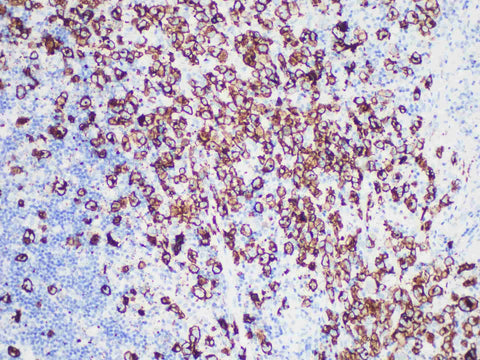

CD30 Monoclonal Antibody Synonyms CD30

Applications IHC-P

Tissue Specificity Tonsil

CD30, a member of the tumor necrosis factor receptor superfamily, is a positive regulator of apoptosis. CD30 is expressed on activated B and T lymphocytes, Hodgkin's lymphoma R-S cells, plasma cells, NK cells, monocytes, and large lymphocytes. CD30 was expressed in classical Hodgkin's disease, anaplastic large cell lymphoma and anaplastic diffuse large B-cell lymphoma. CD30 was also expressed in primary cutaneous CD30-positive lymphoproliferative disease and some mycosis fungoides. CD30 can also be used to distinguish germ cell tumors, which are positive for embryonal carcinoma but negative for seminoma.